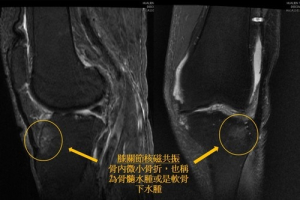

「之前都沒辦法走,一痛就痛。」八十六歲的詹女士,只要從坐姿到站起,左膝就非常疼痛,痛到她不敢動,也不敢走路,疼痛難耐的她,經花蓮慈濟醫院麻醉部疼痛科王柏凱主任為她做骨內注射治療,以不動刀的方式就大幅度的改善膝蓋疼痛,讓詹女士開心分享,現在不只坐下、站起膝蓋沒問題,還可以自己開車上市場買菜。

花蓮慈濟醫院總顧問暨骨科醫師李宏滿教授,12月3日在台灣醫療科技展專家講座,分享「從『膝』望再生到重返運動 再生運動醫學新契機」,讓更多人了解目前最新的膝關節相關治療及再生醫學治療方式,吸引不少民眾前來聆聽講座。